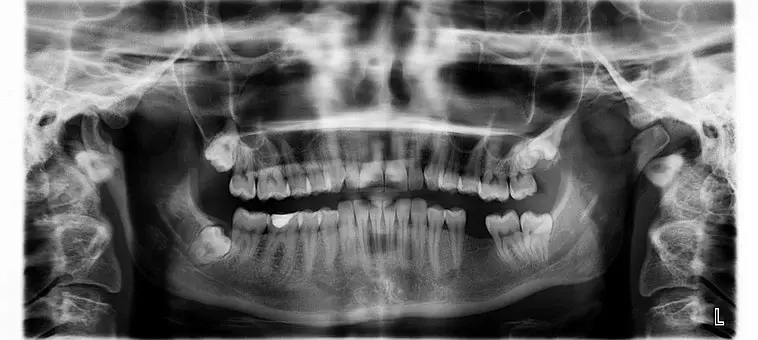

Naj vam obisk pri zobozdravniku ostane v prijetnem spominu. Podjetje ND D.O.O. vam nudi kakovostno implantologijo na Savinjskem.

Nudimo vam odlično implantologijo, kar lahko potrdi veliko naših strank iz Savinjske, ki smo jim že pomagali do lepega nasmeha. A ne le lep nasmeh, zdravo zobovje je pomembno za dobro počutje celotnega telesa.